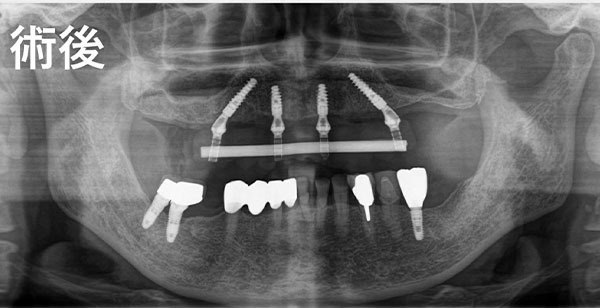

All-on-4は、骨のある部分を正確に選び、適切な角度でインプラントを埋入する高度な技術が必要です。当院では、歯科医師の「経験や勘」だけに頼るのではなく、確実なデータに基づくコンピューターガイデッド手術を行っています。

事前にCTデータを解析し、神経や血管の位置を完全に把握した上で、インプラントの埋入位置を0.1ミリ単位でシミュレーションします。これにより、外科的なリスクを最小限に抑え、長期的に安定する治療計画を立案します。

また、当院では手術本番までに最低でも3回以上のシミュレーション検証を重ねます。徹底的にルートを確認してから臨むため、実際のオペは「リハーサルを経た4回目」のような確実性を持って、スムーズかつ安全に行うことができます。